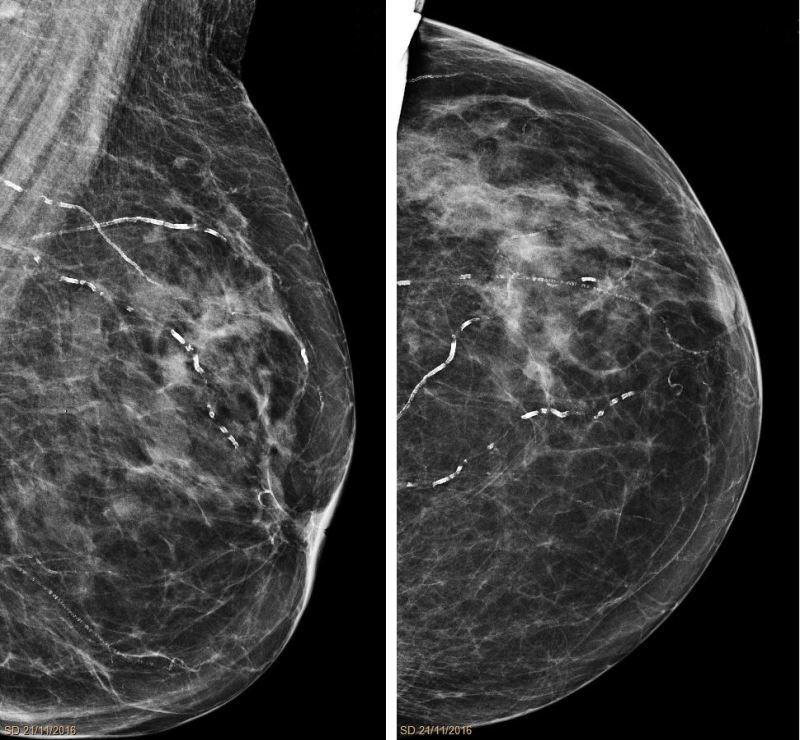

bu ayarlamaya dair iki kıyaslama görüntüsü:

mamografi filmi

burada hastanın göğüs bölgesindeki damarlar ayrı ayrı görülebilmekte, gönderilen dalganın boyu kan dokusunda takılırken diğer dokulardan geçecek şekilde ayarlanmış.